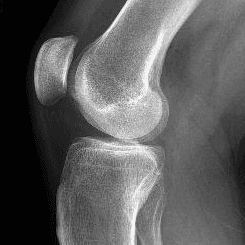

Sağ Diz kapağı

Merhaba Hocam. Diz kapağımda yıllardır beni çok zorlayan bir ağrı var. Merdiven inip çıkarken diz kapağımı büküp açarken ki ağrı çok zorluyor ve belirli dönemlerde çok şiddetleniyor dizimi açıp büktüğümde bazen büyük bir ses oluyor sanki yerine oturuyor gibi oluyor bir şeyler ve ağrısı biraz hafifliyor. Seyahat yaptığımda da çok zorluyor beni. Röntgen de bir şey çıkmıyor MR sonucumda SUPRAPATELLAR YAĞ YASTIKÇIĞINDA HETEROJENİTE VE YAĞ BASKILI PD SEKANSLARDA ÖDEM LEHİNE RETİKÜLER SİNYAL ARTIMLARI İZLENMİŞTİR. yazıyor ve diğer her şey normal bunu yorumlayabilir misiniz rica etsem ? Sol bacağımda da hafif bu belirtiler oluşmaya başladı. Ameliyat olmalık bir durum yoktur umarım. Şimdiden teşekkür ederim.